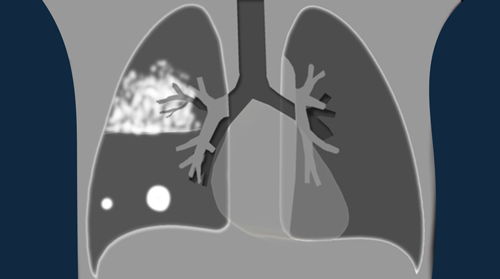

Pulmonary Hypertension and Thromboembolic disease

Pulmonary Hypertension

new